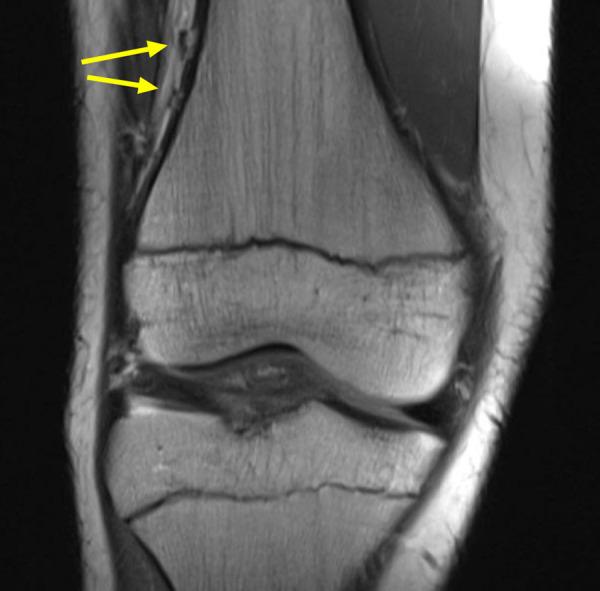

Skeletally immature patients with an acute ACL tear confirmed using MRI within 90 days of injury were assessed. Two fellowship-trained musculoskeletal radiologists independently interpreted each MRI scan twice. KF injury was first assessed using the Van Dyck scheme (grade 0, normal; grade 1, periligamentous; grade 2, partial tear; and grade 3, complete tear). MRI scans were then reviewed again using the KF injury criteria proposed by Batty. Discrepancies in KF injury schemes were adjudicated by a third musculoskeletal radiologist. Interrater agreement for both methods was determined using Cohen κ.

方法

对在受伤90天内通过MRI确诊为急性ACL撕裂的骨骼未成熟患者进行评估。两名接受过专科培训的肌肉骨骼放射科医生分别对每次MRI扫描进行两次独立解读。首先使用范戴克方案评估KF损伤(0级,正常;1级,韧带周围;2级,部分撕裂;3级,完全撕裂)。然后使用巴蒂提出的KF损伤标准再次审查MRI扫描。KF损伤方案的差异由第三位肌肉骨骼放射科医生进行判定。使用科恩κ系数确定两种方法的评分者间一致性。